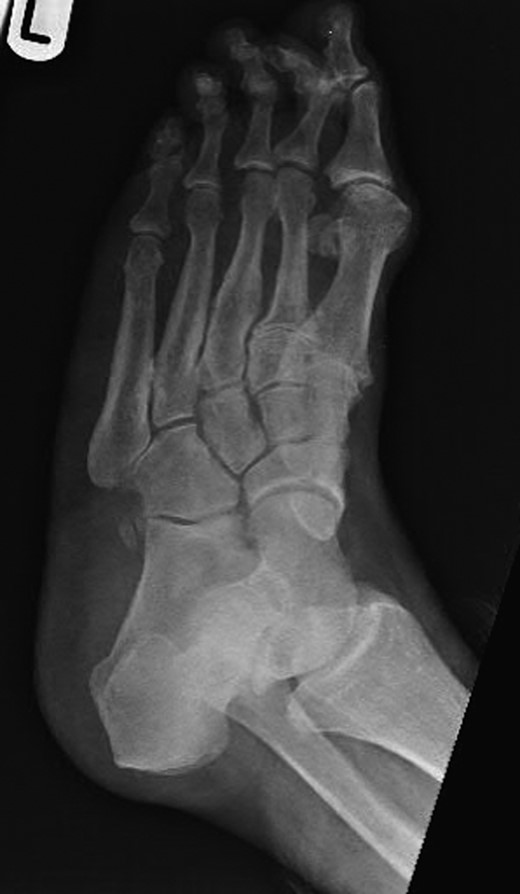

Dorsoplanter, lateral and oblique radiographs demonstrated an additional bone immediately distal to the middle cuneiform articulating with the second metatarsal base and middle cuneiform. Second and third metatarsals were shorßt in comparison with normal (Figs 1–3). Osteoarthritis was seen in all TMTJs and the first MTPJ. A computed tomography (CT) scan confirmed the presence of the additional bone and degenerative joint disease (Figs 4 and 5).

Dorsoplanter radiograph of the left foot with the clearly visible additional middle cuneiform.